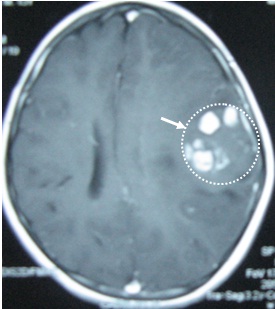

Chụp MRI sọ não phát hiện tại thuỳ thái dương trái có 3 khối u kích thước các khối 1,5 x 1,5 cm, ngoài ra còn có các u kích thước nhỏ xung quanh. Hình ảnh MRI gợi ý đến hình ảnh u Lympho não hơn là di căn não. Bệnh nhân được chỉ định mở sọ não lấy u làm giải phẫu bệnh nhưng bệnh nhân đã từ chối phẫu thuật.

VàoTrung tâm YHHN&UB, Bệnh viện Bạch Mai, bệnh nhân được chỉ định làm thêm xét nghiệm chuyên khoa Xạ hình bạch mạch với Fyton - Tc-99m (ghi hình với máy SPECT),

(Hình ảnh xạ hình bạch mạch bằng máy SPECT với

Fyton-Tc-99m )

Kết quả: phát hiện thấy có tổn thương hạch thượng đòn bên trái kích thước khá nhỏ (trên lâm sàng không sờ thấy được).

Tiến hành sinh thiết tổ chức thượng đòn (ST Daniel) lấy ra đựợc một hạch kích thước 0,6 cm, chắc, ranh giới rõ, gửi làm xét nghiệm giải phẫu bệnh , kết quả là U lympho ác tính không Hodgkin, tế bào lớn lan toả (WF7)

Bệnh nhân được tiến hành điều trị hoá chất phác đồ CHOP 8 đợt và tiêm Methotrexat nội tuỷ, kết quả u sọ não tan hoàn toàn. Đến nay, bệnh nhân đã được ra viện 10 tháng. Hiện tại vẫn khoẻ mạnh, chụp MRI sọ não không phát hiện ra khối u.

Đây là một ca lâm sàng hay, một tình huống chẩn đoán khó khăn, nhờ có kỹ thuật YHHN phát hiện tổn thương hạch thượng đòn mặc dù kích thước còn rất nhỏ, rất dễ bỏ sót bằng thăm khám lâm sàng. Bệnh nhân rất may mắn không phải chịu cuộc đại phẫu mở sọ não lấy u làm xét nghiệm giải phẫu bệnh mà vẫn có hướng điều trị đúng đắn.